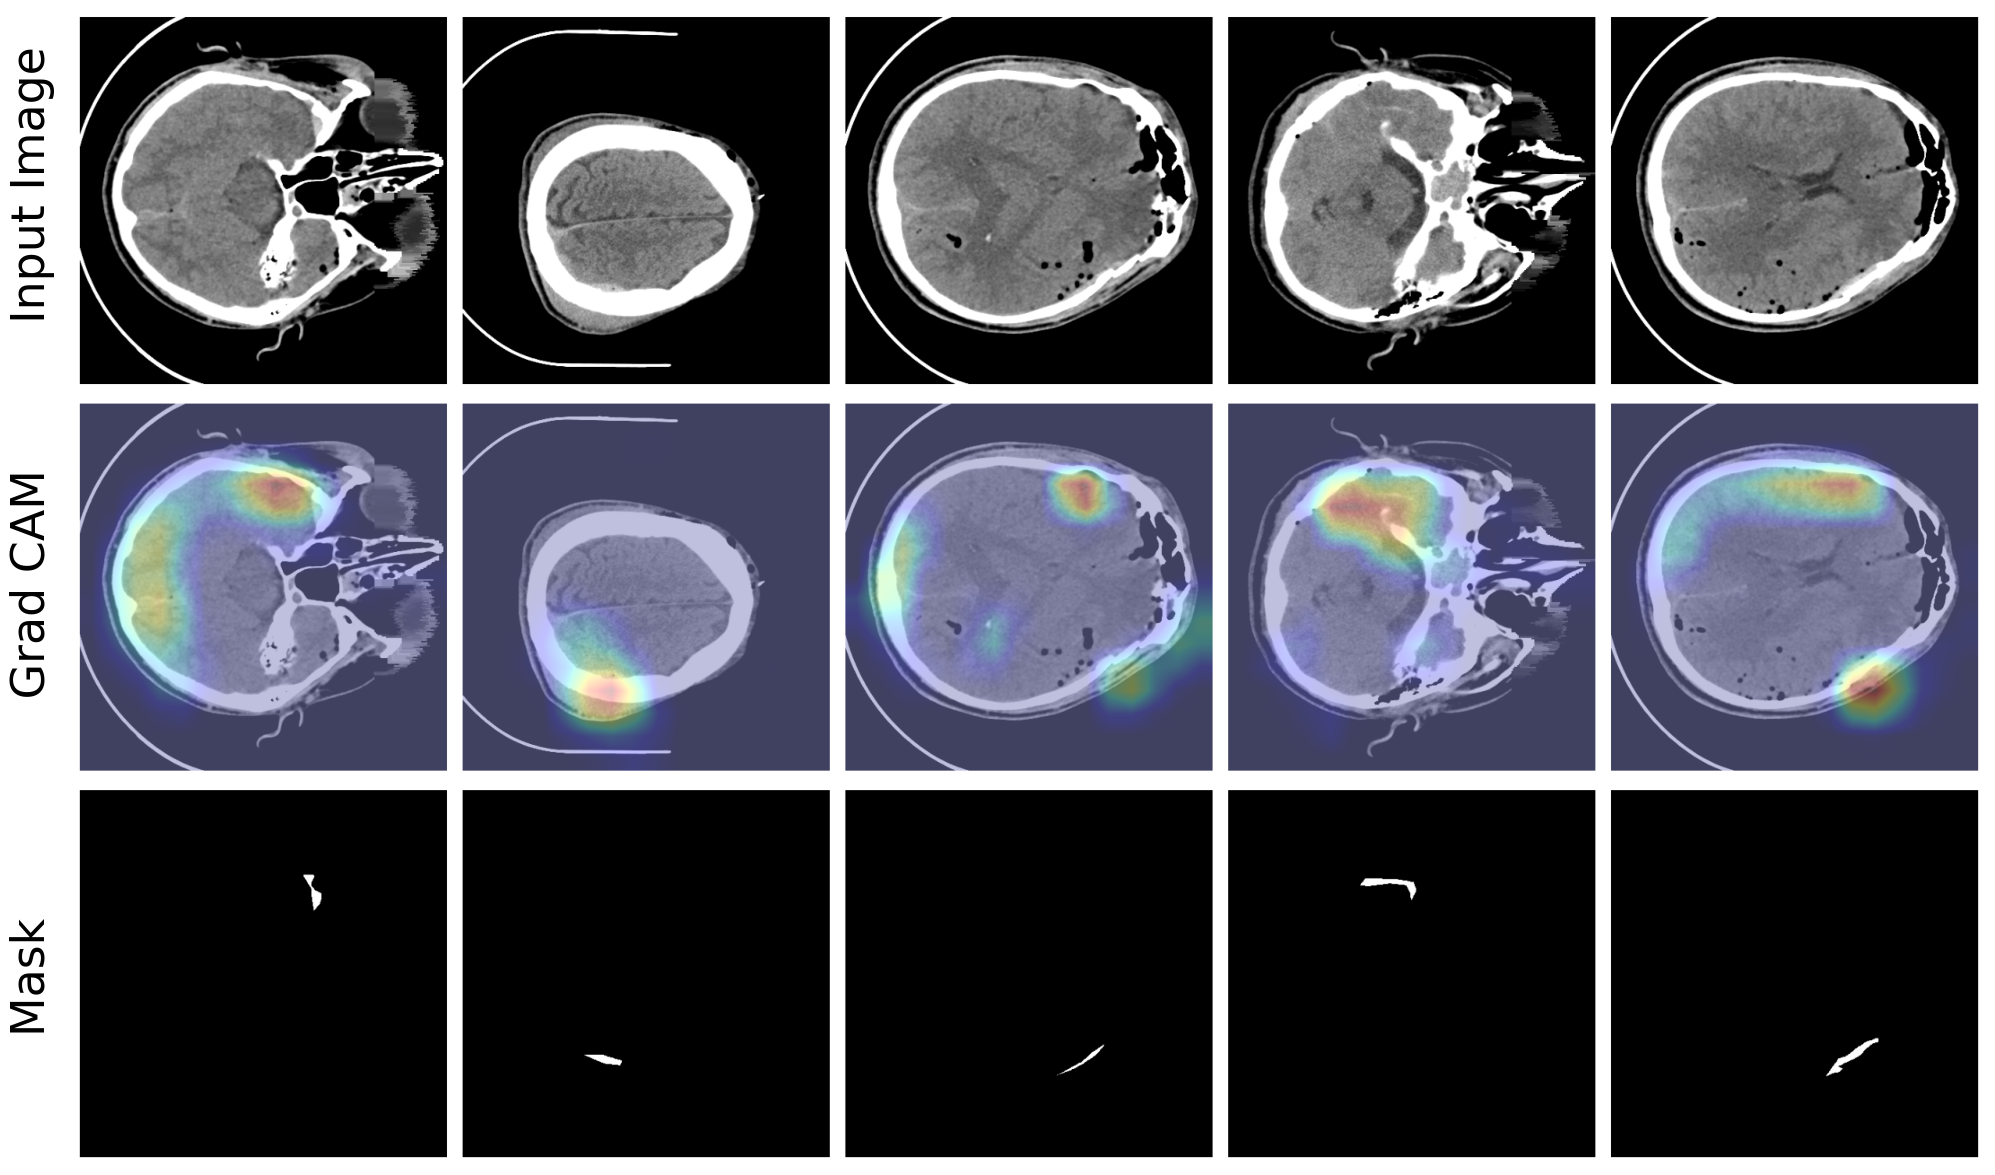

ICH Detection, Classification, Segmentation

The project focused on classifying, detecting, and segmenting hemorrhagic lesions in CT scans using a novel multi-step approach. We developed a multi-step method primarily aimed at increasing the performance of the segmentation process for 3D medical images. The approach includes the development of a novel post-processing method to refine segmentation outcomes, as well as a trainable pre-processing technique to enhance input data quality before model training. Ongoing research explores models like Vision Transformers (ViTs) and sequential models such as RNN and GRU within this framework. To enhance interpretability and explainability for medical specialists, we are developing a decision policy based on fuzzy systems. We also conducted a comprehensive statistical review of the datasets to uncover meaningful patterns within the available data. A key achievement was the creation of a custom dataset of over 900 patient CT scans for segmentation and quantification of intracerebral hemorrhage volume, in collaboration with Iran Medical University and Rasool Akram Hospital. Explainability tools like GradCAM were integrated to improve model transparency, followed by t-SNE transformations to visualize high-dimensional data and model behavior more effectively. This project was my bachelor thesis, resulting in one published paper and another currently in progress. I served as the technical manager of research and development for this project at APAC group.